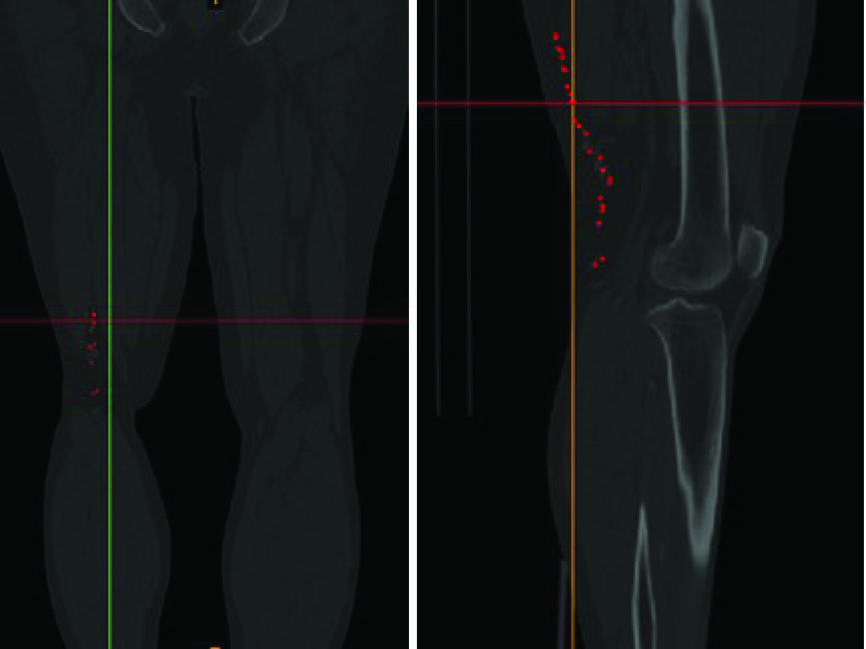

In the present study, the computational fluid dynamics (CFD) simulation of the blood flow within the corkscrew collateral artery of the Buerger’s disease is performed. The geometrical modeling of the artery is obtained based on the actual configurations of the corkscrew collateral of a 40 year old male patient with the Burger’s disease. Fig. 1 is the CT-angiography image of the patient’s leg. The location of the corkscrew artery is represented by red dots. The blood properties that are used in the presented simulation are the same as the actual blood properties of the patient. Flow patterns, velocity contours, pressure and kinematic viscosity in different segments of the corkscrew artery are studied and discussed further in the results and discussion section.

Fig. 1 .

The CT-angiography of the patient’s leg. The location of corckscrew collaterals are displayed by red dots.